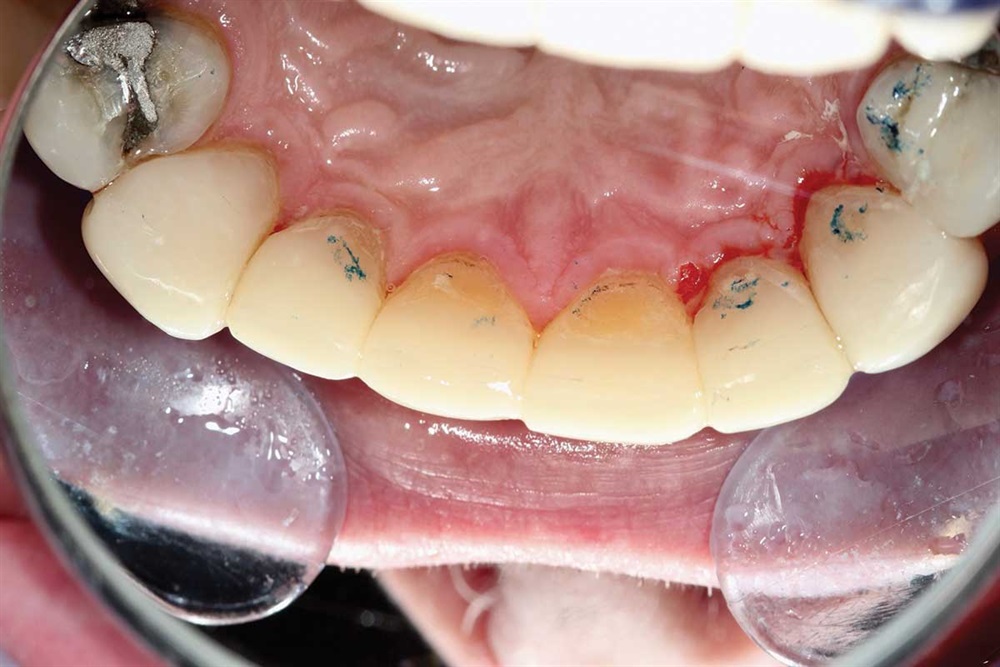

Show Your Work

Fig. 21: September 2018. First picture from his second go-round. Not brushing the lowers well.